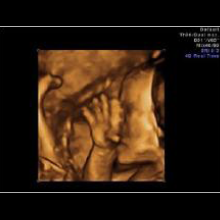

Eine ganz besondere Faszination bieten die neuen 3D/4D Ultraschallgeräte.

Die 3D-Sonografie erlaubt die einzigartige räumliche Darstellung des ungeborenen Kindes. In der 4D-Technik werden Bewegungsabläufe in nahezu fotorealistischer Weise in Echt-Zeit (Real-Time) mit bis zu 25 Bildern/sec. möglich- ein faszinierender Einblick in die Welt des Ungeborenen.

HIER EINE AUSWAHL VON 3D-ULRASCHALL-BILDERN: